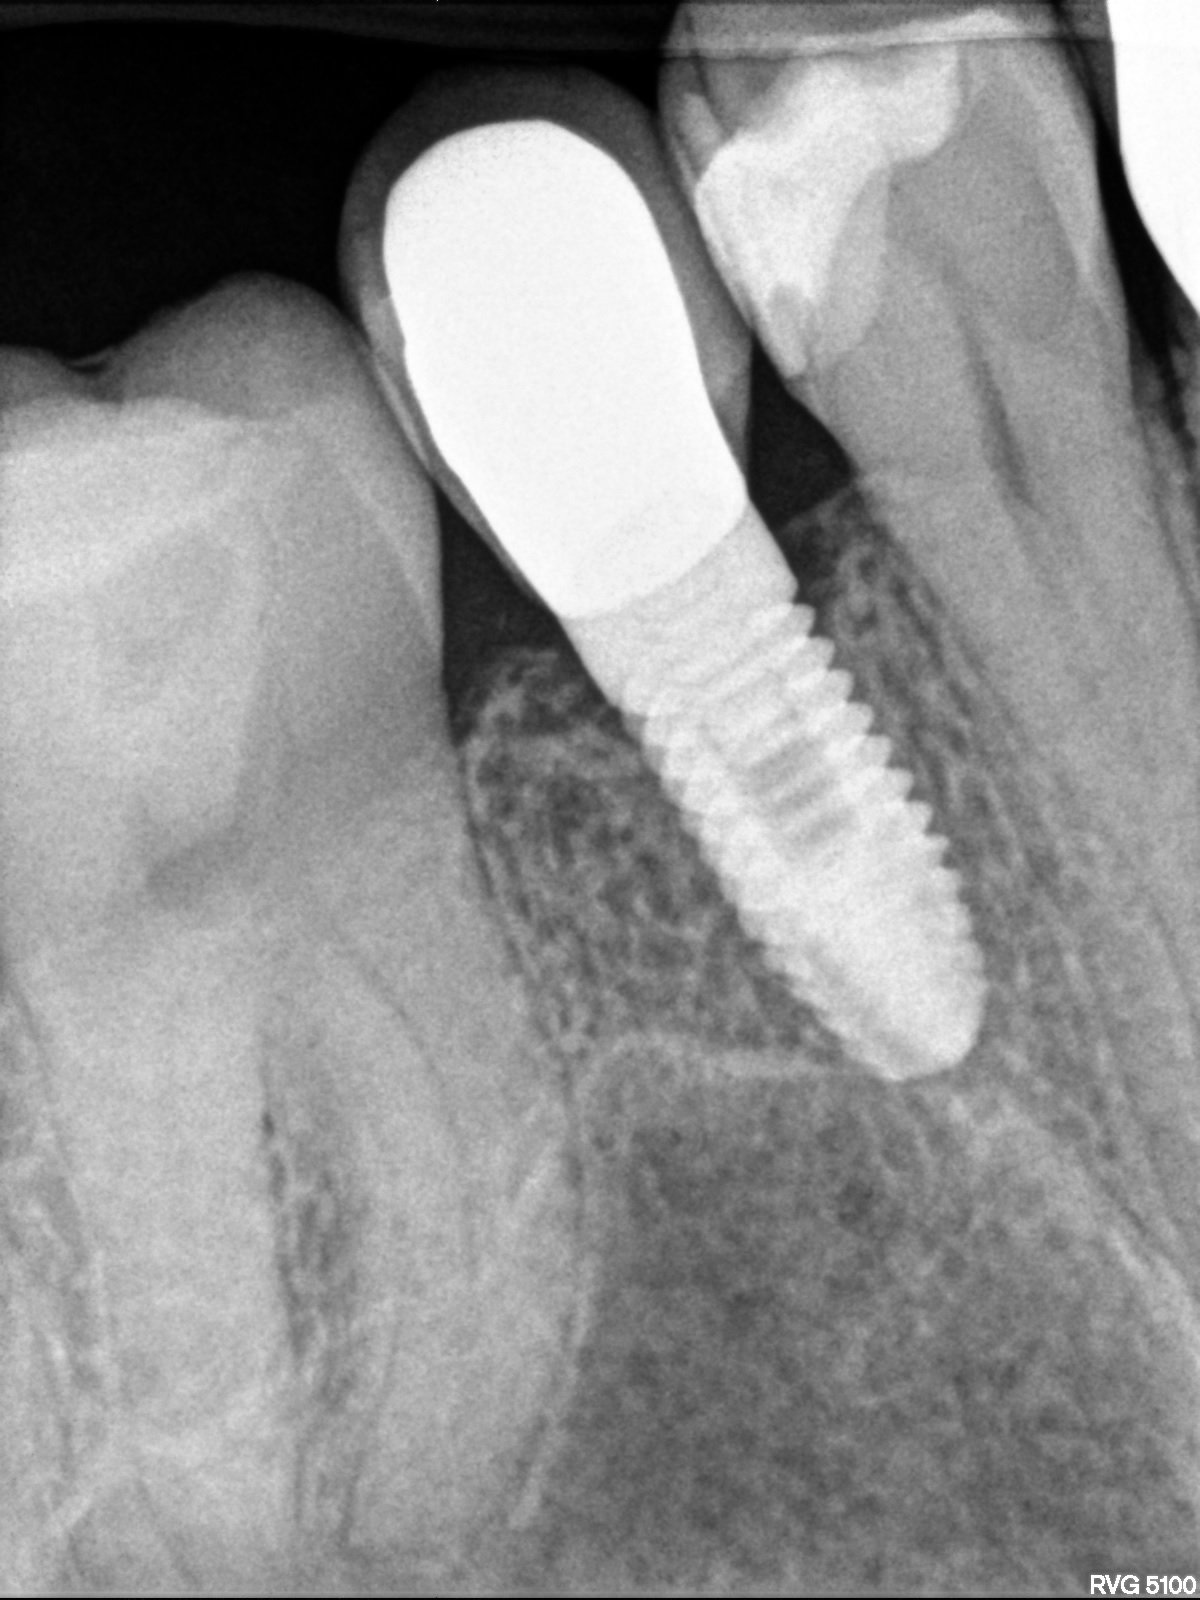

Implante con 20 años, dice el paciente. el tornillo de cicatrización no es el suyo, le pusieron uno que tenia por ahí. muchas gracias compañeros.

Buenas tardes!! Podríais ayudarme con este implante en p. 21, marca y diámetro?? Muchas gracias!!